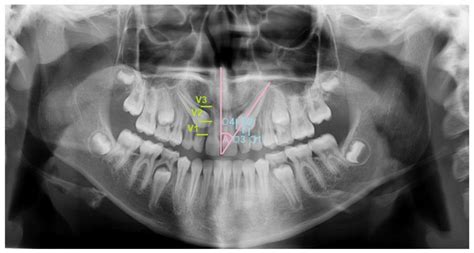

In many cases, an impacted canine tooth does not cause immediate pain, which is why regular dental check-ups are vital. Dentists often identify the issue during routine X-rays long before a patient experiences symptoms. However, as the condition progresses, you might notice specific indicators that suggest something is amiss within your gum tissue.

⚠️ Note: If you notice any of these signs, consult an orthodontist immediately to determine the position of the tooth using 3D imaging or panoramic X-rays.

Treating an impacted canine tooth usually requires a collaborative effort between your general dentist, an orthodontist, and an oral surgeon. The goal is to bring the tooth into its natural position to complete your smile. Treatment plans are highly individualized based on the tooth's specific angulation and depth within the bone.

Early detection is the most effective way to prevent these issues. By visiting an orthodontist by age seven, children can be evaluated for potential impaction issues. Early intervention, such as the extraction of baby teeth to create space, can often encourage the permanent canine to erupt naturally, bypassing the need for complex surgical exposure entirely.